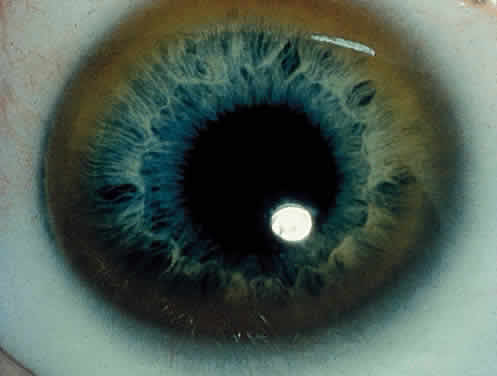

OCULAR FINDINGS. The outstanding clinical feature common to all three phenotypes is the corneal and conjunctival cystine crystal deposition (Figs. 3 and 4). Photophobia is often the only presenting visual symptom; this may be incapacitating and associated with blepharospasm.

Corneal deposits appear as a layer of homogeneously distributed, fusiform or needle-shaped, iridescent crystals situated in the stroma beneath the epithelium. In the infantile form, anterior crystal deposition begins early in life (between 6 and 15 months of age) and proceeds posteriorly as the patient ages; deposition advances more rapidly in the periphery. The anterior location of the crystals may be associated with recurrent erosions.33 The depth of the stromal deposition and the density of crystals is always greater peripherally than centrally. More and larger crystals occur in the superficial stroma. No visual impairment occurs at this early stage. By the age of 7 years, most patients have crystals, either within or on the endothelial surface34,35; markedly decreased corneal sensitivity is also present.36 The spherical contrast sensitivity function is significantly lower in infantile cystinosis than in age-matched controls.37

The conjunctiva has a ground-glass appearance. Polychromatic, polymorphic, rectangular, or rhomboidal crystals can be seen with the biomicroscope.

The uvea contains an abundance of polymorphous crystals. Clinically, these can be seen as glistening dots on the surface of the iris. Thickened iris stroma and posterior synechiae may occur; pupillary block glaucoma38 also has been reported. The entire uvea has polymorphic crystal deposition, most heavily in the choroid. The sclera also has crystal deposition.